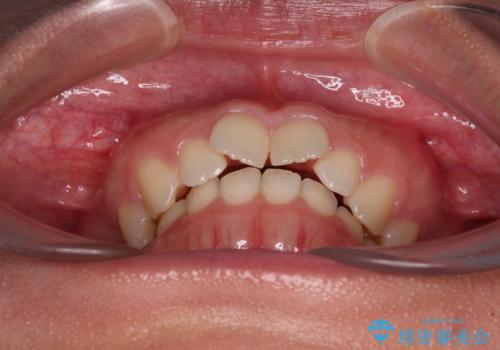

- 上下前歯のデコボコを気にして来院された患者様です。

上顎歯列が下顎の歯列に対して狭小であり、一部下顎の奥歯が上顎よりも外側に位置している状態でした。

上顎の急速拡大装置を使用して上顎骨を側方に拡大することで上顎歯列を拡大し、下顎歯列も拡大できるようにすることで、歯列を整えることとしました。

歯列矯正では基本的に骨格を改善することはできませんが、急速拡大装置(MARPE)を使用することで上顎骨を側方に拡大させることができ、咬合状態を大きく改善することができます。